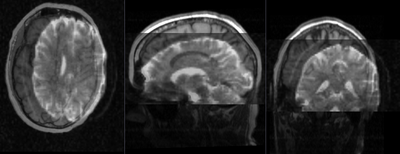

this is the fixed reference image. All images are aligned into this space this is the fixed reference image. All images are aligned into this space lleft lleft this is the T1 moving image

fixed image

DTI

DTI baseline

moving image

T1 SPGR